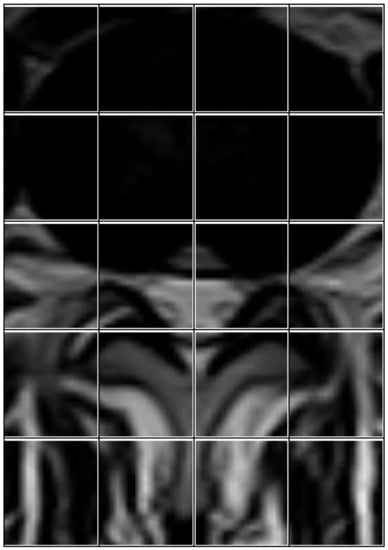

The process of analyzing medical images is very complex and often the parts in the image overlap with the object to be diagnosed. For example, in the process of diagnosing images of lumbar spine discs, there are many shapes in the image such as the image of the intervertebral disc; the same is true in the diagnosis of spinal cord stenosis. Therefore, we proposed the ROI technique, which splits the image into many blocks, and we were able to identify the most important blocks. We divided the image with size (1061 width * 752 height) into 104 blocks and then selected 20 blocks with ROI, each of which has a size (82 * 94). Finally, we chose 20 blocks based on Equation (3).

where Z represents the block number to be selected. After completing this process, we obtained images that contain only the area of interest (see Figure 6). In Figure 7, we illustrate the steps to create ROI images.

Figure 6. Twenty blocks from an image, each one with size (82 * 94) used to create ROI.